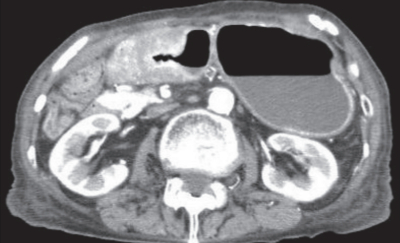

血液所見:赤血球 392 万、Hb 10.9 g/dL、Ht 36 %、白血球 4,100、血小板 22 万。血液生化学所見:総蛋白 5.8 g/dL、アルブミン 3.2 g/dL、総ビリルビン 0.5 mg/dL、AST 22 U/L、ALT 8 U/L、γ-GT 11 U/L(基準 8 ~50)、尿素窒素 22 mg/dL、クレアチニン 0.8 mg/dL、Na 131 mEq/L、K 3.4 mEq/L、Cl 96 mEq/L、CEA 16.4 ng/mL(基準 5 以下)、CA19-9 180 U/mL(基準 37 以下)。腹部造影 CTを別に示す。幽門狭窄を伴う胃癌と診断し、10 日間の栄養投与後に手術を行うこととした。